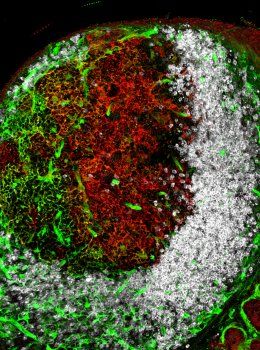

The Wonderful World of 3D+